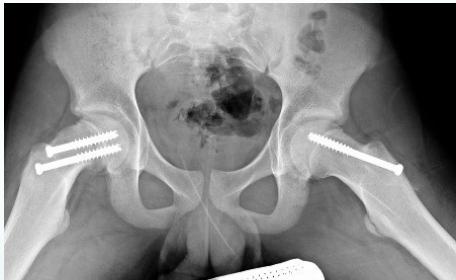

Treatment:

- Critical principle: Manipulation to reduce the slip may cause avascular necrosis (AVN)

- Surgical management:

- Fixation in situ (without reduction)

- Prophylactic fixation: Consider fixing the contralateral hip (1/3 will develop slip on other side)

Complications:

- Avascular necrosis (AVN)

- Coxa vara

- Slippage of opposite hip

- Secondary osteoarthritis

(Source: BMJ Best Practice)